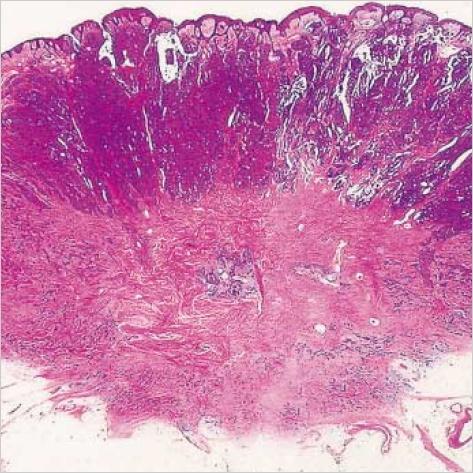

Syringocystadenocarcinoma papilliferum (SCACP) is a rare form of adenocarcinoma of the skin. This is the malignant counterpart of syringocystadenoma papilliferum (SCAP) and usually develops on the scalp in a long-standing lesion identified clinically as SCAP. We describe a 65-yr-old Korean man with a nodule on the right supra-pubic area with a 2-yr duration. Histologically this tumor had a similar overall configuration as in SCAP, but the tumor was asymmetric and poorly circumscribed, extending into the deep dermis and showed cytologic atypia. The tumor cells showed positive reaction to GCDFP-15, but negative reaction to CEA and HMFG-1. We established the diagnosis of SCACP in the patient, and a wide excision was performed to remove the tumor. The patient has been well without relapse or metastasis for 2 yr.

乳头状汗管囊腺癌(SCACP)是一种罕见的皮肤腺癌。它是乳头状汗管囊腺瘤(SCAP)的恶性对应物,通常发生于头皮上临床上诊断为SCAP的长期病变处。我们报告一名65岁的韩国男性,其右侧耻骨上区有一个持续2年的结节。组织学上,该肿瘤的总体结构与SCAP相似,但肿瘤不对称且边界不清,延伸至真皮深层并显示细胞异型性。肿瘤细胞对GCDFP - 15呈阳性反应,但对CEA和HMFG - 1呈阴性反应。我们确诊该患者为SCACP,并进行了广泛切除以切除肿瘤。该患者2年来情况良好,无复发或转移。